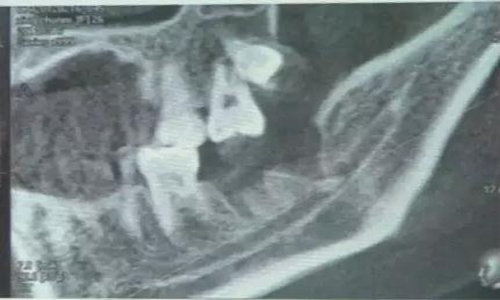

用到4號牙挺,避免敲擊拔牙根,稍有不慎,可能會出現(xiàn)牙根移位下頜神經(jīng)管。

術(shù)中拍片發(fā)現(xiàn),還有剩余,繼續(xù)。。。。